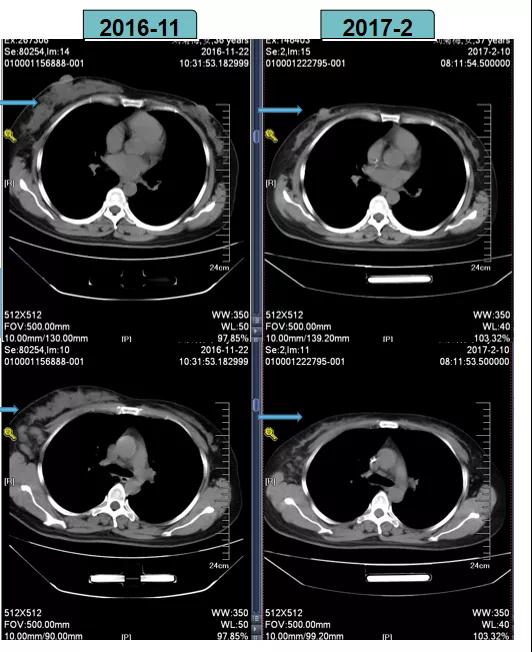

TCbH方案进行新辅助化疗后,患者疗效评估为PR

2017-2-10全麻下行右乳癌改良根治术。

影像学评估-纵膈淋巴结: